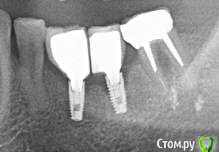

витаХА Опубликовано 30 октября, 2015 Автор Поделиться Опубликовано 30 октября, 2015 Нашёл снимок. Попробывал сфотать и вот что получилось. Кстати ,может кто нибудь в Москве возьмётся проконсультировать меня очно на предмет состояния кости(не бесплатно конечно).Коронки сейчас на временых пломбах и винты на них закручены отверткой,а не ключом - так что открутить их и посмотреть на импланты не составит большого труда. Ссылка на комментарий

diesel87 Опубликовано 30 октября, 2015 Поделиться Опубликовано 30 октября, 2015 Нашёл снимок. Попробывал сфотать и вот что получилось. Кстати ,может кто нибудь в Москве возьмётся проконсультировать меня очно на предмет состояния кости(не бесплатно конечно).Коронки сейчас на временых пломбах и винты на них закручены отверткой,а не ключом - так что открутить их и посмотреть на импланты не составит большого труда.Так тут изначальные проблемы с костью, до этапа протезирования. Ссылка на комментарий

витаХА Опубликовано 30 октября, 2015 Автор Поделиться Опубликовано 30 октября, 2015 Так тут изначальные проблемы с костью, до этапа протезирования. Ёпрст,так значит этот врач должен был изначально видеть проблему с костью и сказать об этом мне,но он не взирая на это всё равно берётся за протезирование,так что ли?????Блин, я в ауте!!!А сейчас то что то можно решить с этой проблемой или уже как говорится - расслабиться и получать удовольствие??? Ссылка на комментарий

diesel87 Опубликовано 30 октября, 2015 Поделиться Опубликовано 30 октября, 2015 Ёпрст,так значит этот врач должен был изначально видеть проблему с костью и сказать об этом мне,но он не взирая на это всё равно берётся за протезирование,так что ли?????Блин, я в ауте!!!А сейчас то что то можно решить с этой проблемой или уже как говорится - расслабиться и получать удовольствие???Я так понял импланты вы ставили в одной клинике, а протезирование в другой? Вам перед началом протезирования делали снимки во второй клинике? Этот снимок на каком этапе? Ссылка на комментарий

витаХА Опубликовано 30 октября, 2015 Автор Поделиться Опубликовано 30 октября, 2015 Я так понял импланты вы ставили в одной клинике, а протезирование в другой? Вам перед началом протезирования делали снимки во второй клинике? Этот снимок на каком этапе?Да,именно так.Делали во второй и соответственно последней, во всей этой истории, клинике. Делали на этапе консультации перед самым началом протезирования. Ссылка на комментарий

Larnary Опубликовано 2 ноября, 2015 Поделиться Опубликовано 2 ноября, 2015 (изменено) У меня большие сомнения,что абатменты посажены до конца. И в этом вижу первопричину. Ну а неправильно изготовленные коронки добавили проблем сверху. Соавните со снимком,где формирователи Изменено 2 ноября, 2015 пользователем Larnary 2 1 Ссылка на комментарий